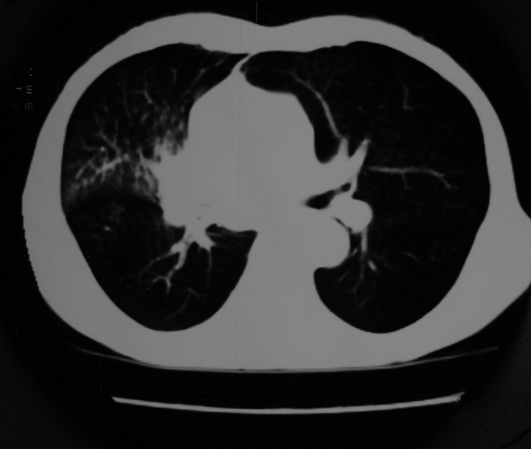

以下是引用同在2007-1-27 14:13:00的发言:[br]支持右侧中央型肺癌伴阻塞性病变.

以下是引用zjzjr在2007-1-27 16:56:00的发言:[br]支持右肺中心型肺癌伴阻塞性肺炎.